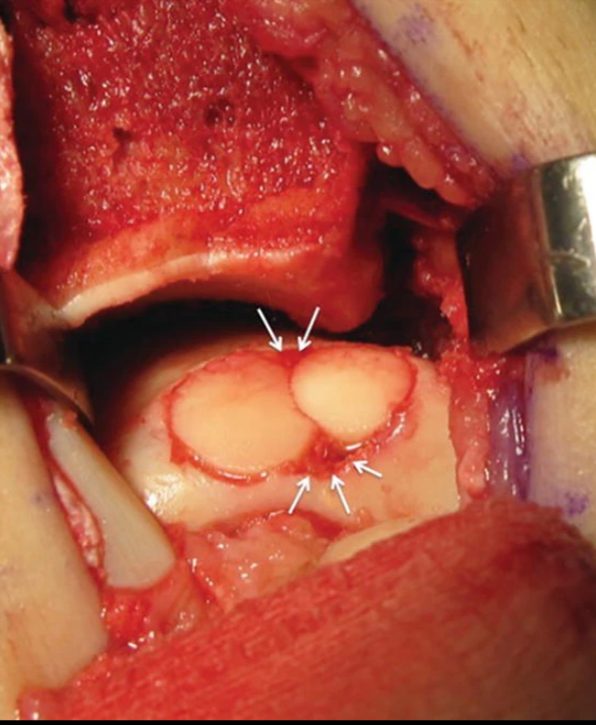

Аутологичная остеохондральная трансплантация (OCT / OATS)

Техника:

- Забор остеохондрального цилиндра (6-10 мм в диаметре) из ненагружаемой зоны медиального мыщелка бедренной кости или межмыщелковой ямки

- Подготовка реципиентного ложа на таранной кости — формирование гнезда под цилиндр. Требуется строго перпендикулярный доступ к дефекту, поэтому часто необходима остеотомия внутренней лодыжки

- Имплантация цилиндра — press-fit фиксация, без дополнительных имплантов. Цилиндр должен быть заподлицо с окружающим хрящом (± 1 мм)

- Фиксация остеотомии (2 канюлированных винта)

- При множественных/крупных дефектах — мозаичная пластика (mosaicplasty): несколько цилиндров меньшего диаметра

Рис. 12. Мозаичная остеохондропластика (OATS) — пересадка остеохондральных цилиндров